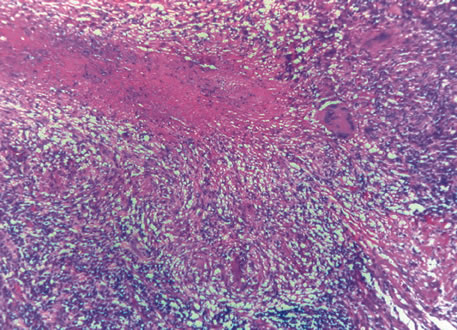

Inflammatory conditions may also lead to iris nodules. Patients suffering from fungal endophthalmitis may demonstrate an irregular yellow-white mass on the iris. Histologically, these appear as necrotizing granulomas containing mycotic agents (Fig. 2). In juvenile xanthogranuloma, a yellowish-gray iris lesion may be associated with spontaneous hyphema, and histopathologically the nodules demonstrate diffuse histiocytic infiltrate (Fig. 3). Multinucleated giant cells displaying peripheral foamy cytoplasm are also noted; these cells are known as Touton giant cells.29 The giant cells and the histiocytes contain lipid that can be demonstrated by oil red O stain.

Fig. 2. Coccidioidomycosis. Iris stroma shows necrotizing granuloma containing mycotic organisms. The organisms show features of Coccidioides immitis. (Hemotoxylin-eosin ×60.)